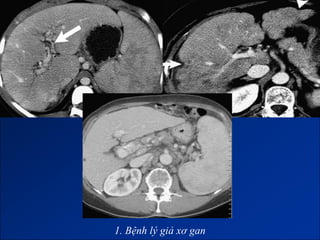

1. Bệnh lý giả xơ gan (Micmic cirrhosis).

1. Bệnh lý giả xơ gan

• #84 Bệnh lý giả xơ gan do - Congenital hepatic fibrosis (phì đại HPT I và thùy bên gan trái, teo gan phải, HPT IV bình thường) - Di căn từ ung thư tuyến vú (phì đại HPT I, bờ gan không đều) - U hạt ở gan (thường phải sinh thiêt). - HC Budd-Chiari (phì đại HPT I, dấu hiệu TALTMC, ).

• #85 Bệnh lý giả xơ gan do - Congenital hepatic fibrosis (phì đại HPT I và thùy bên gan trái, teo gan phải, HPT IV bình thường) - Di căn từ ung thư tuyến vú (phì đại HPT I, bờ gan không đều) - U hạt ở gan (thường phải sinh thiêt). - HC Budd-Chiari (phì đại HPT I, dấu hiệu TALTMC, ).